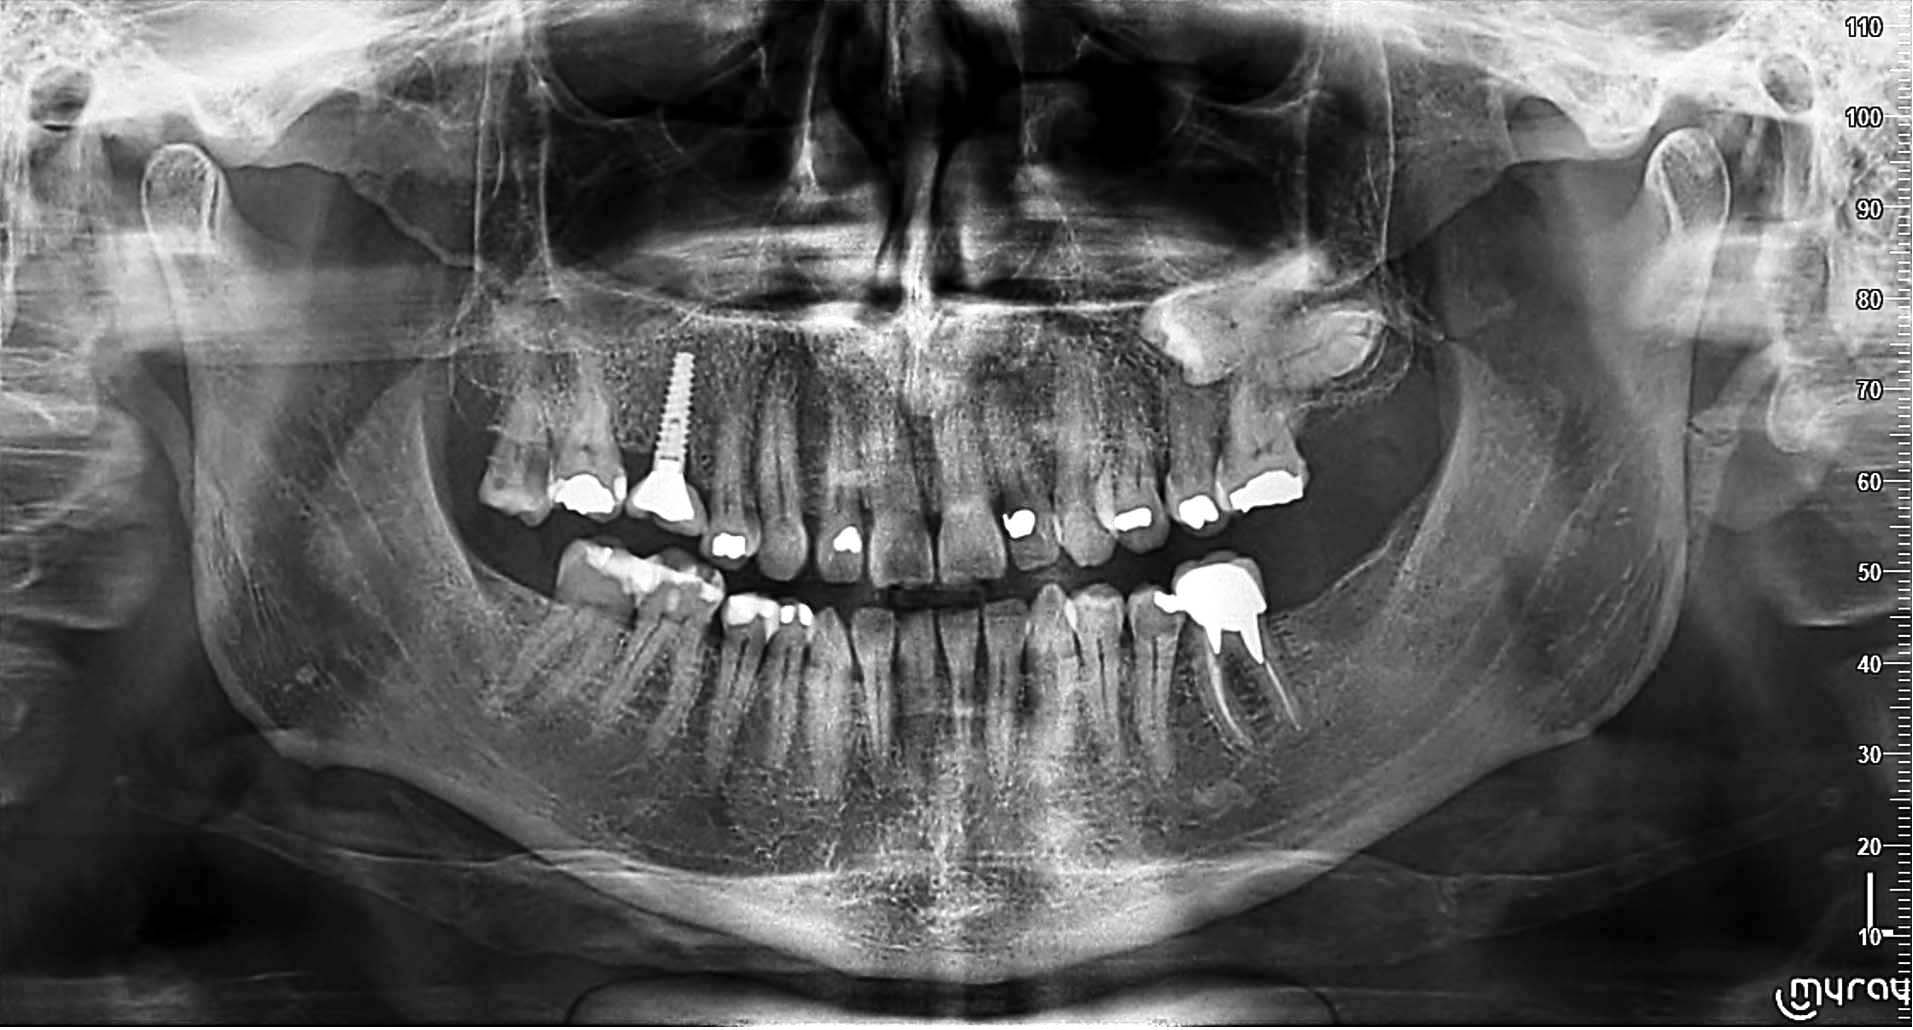

Yeni nesil hassas Cmos Flat Panel Teknolojisi. Görüntü kesitleri eskiye göre 2 kat daha keskin ve net görüntü almayı sağlamaktadır. Panoramik görüntülemede devrim yaratan Panoral 5 MultiPan çekim tekniği ile tek panoramik doz ile 5 ayrı katmanda görüntü alınır. Reel 16 bit yüksek gri skalası ile yüksek çözünürlük ve kesin tanı imkânı sunmaktadır. PANORAL 5 MULTIPAN Panoramik Röntgen Çekim Tekniği: CMOS Flat Panel Hassas Sensör teknolojisi tek bir panoramik doz ile horizontal düzlemde 3 mm. aralıkla, hastanın 5 ayrı vertikal panoramik görüntüsünün elde edilmesini sağlamaktadır. Bu şekilde net alan derinliğine girmeyen bir diş var ise bir önceki veya bir sonraki filmde görülebilir. Panoral 5 MULTIPAN görüntüleme tekniği; maloklüzyon ve hasta pozisyonlandırma hataları nedeniyle oluşabilecek görüntü bozukluklarını elemine edebilmektedir. Böylelikle panoramik röntgen çekimlerinde pozisyonlandırma hatalarına bağlı çekim tekrarlarına da gerek kalmaz.

• Radyo-opak yansımaları ortadan kaldıran özellik • Doldurulmuş kanal yansımaları eleminasyonu • İmplant yansımaları eleminasyonu • Amalgam ve restorasyon yansımaları eleminasyonu